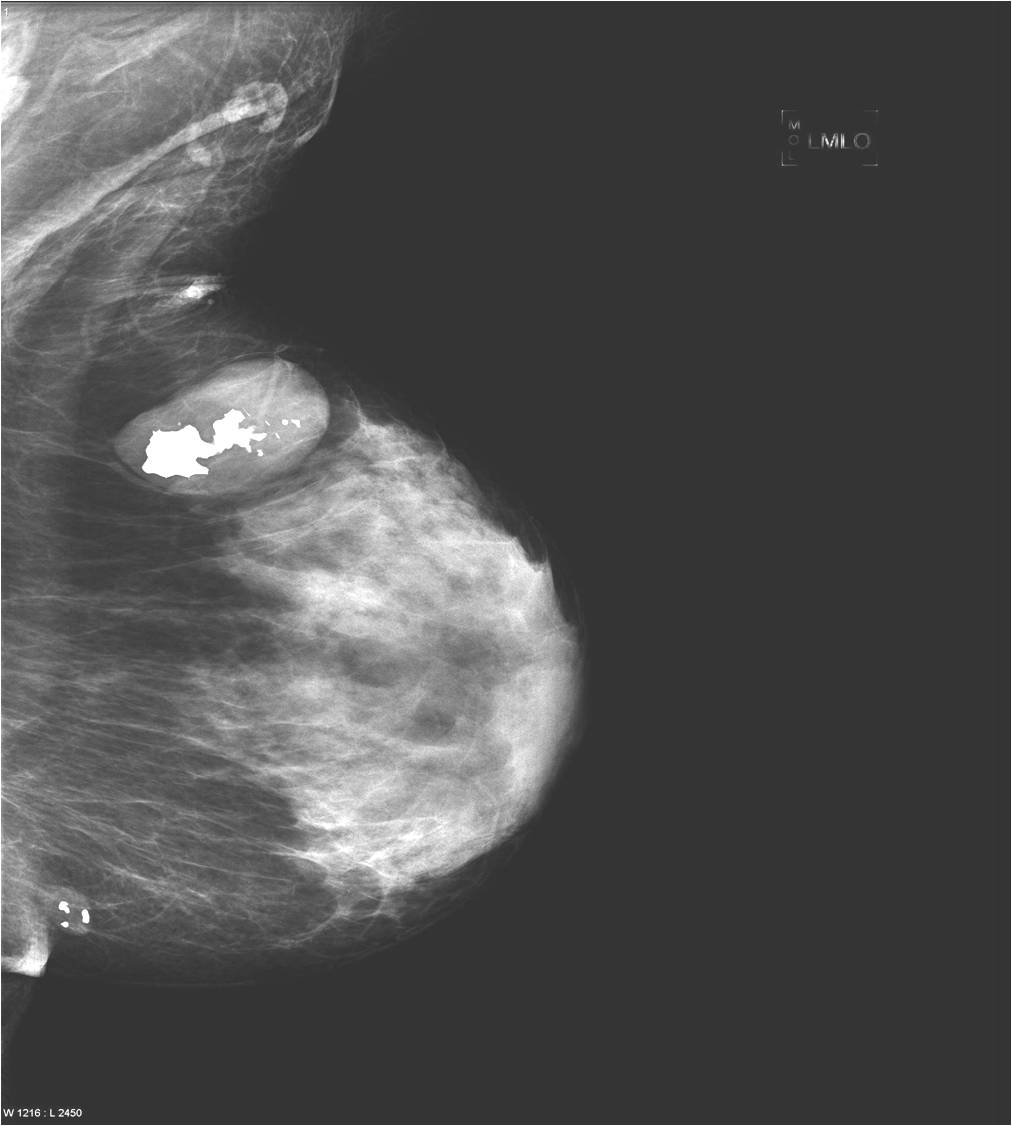

Calcifications appearing in the breast:

Calcifications usually occur in the secretions or in the necrotic parts of the lesions, but they can also be found within the arterial walls or old hematomas as well as scar tissues. (Picture 22.)

Calcifications are encountered in the breast quite often. Most of them accompany benign process (Picture 21.) and only a smaller percentage actually indicates malignancy. These malignant signs are basically always micro-calcifications. They are ill-shaped, with various pleomorphism (Pictures 23.,24.) and they are usually show a clustered arrangement. Their number is irrelevant to the grade of malignancy. Their analysis with mammography is often hard, but targeted and magnified images can help in it. In most the cases these lesion can’t be identified with ultrasound, so stereotaxy core biopsy is needed.